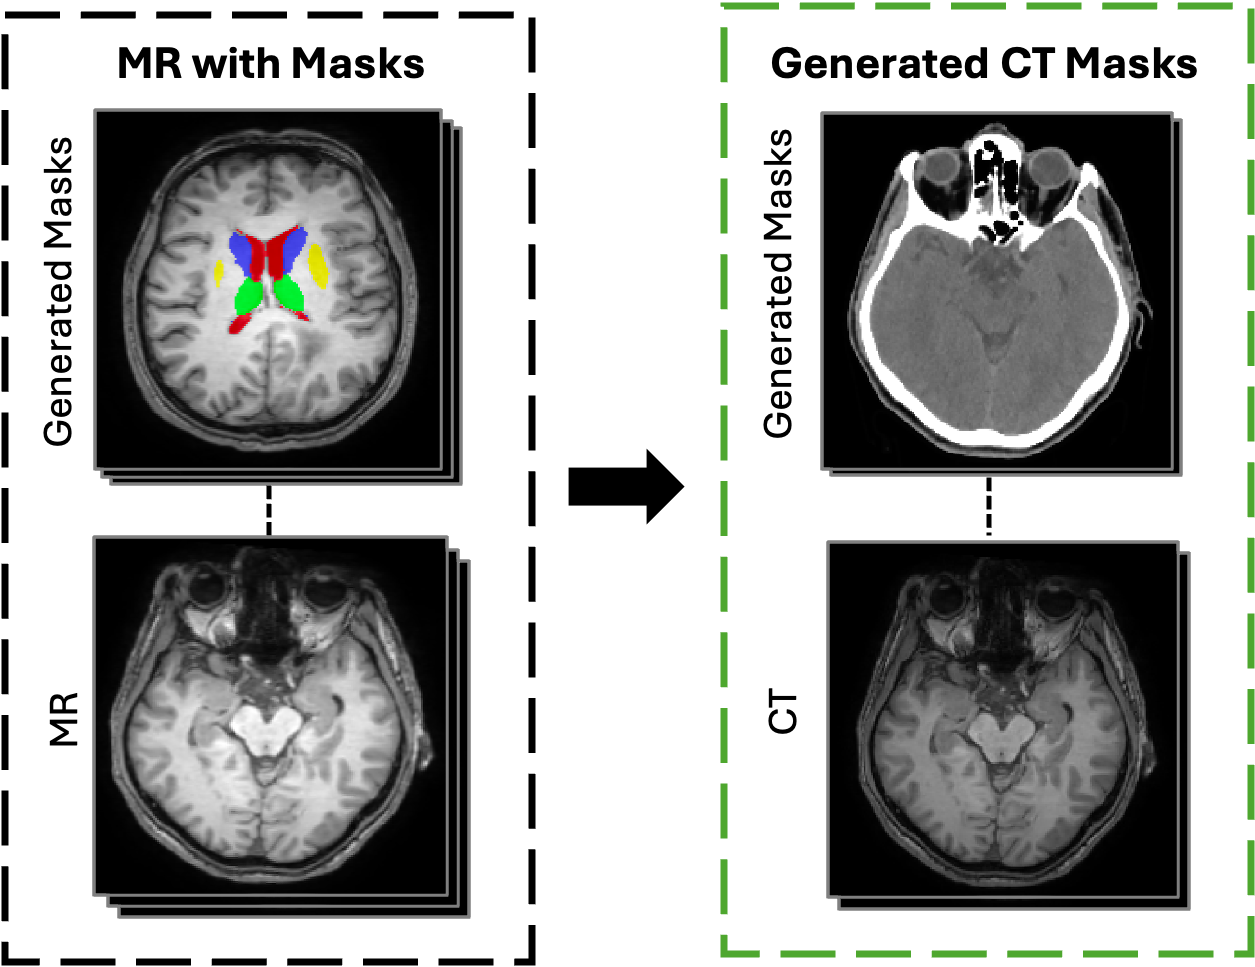

Subcortical Masks Generation in CT Images via Ensemble-Based Cross-Domain Label Transfer

Augustine XW Lee*, Pak Hei Yeung*, Jagath C Rajapakse

Annual Conference on Medical Image Understanding and Analysis (MIUA), 2025 (Oral)

paper / code / bibtex

An automatic ensemble framework to generate subcortical segmentation labels for CT scans by leveraging existing MRI-based models, providing the first publicly available annotated CT dataset in the field.